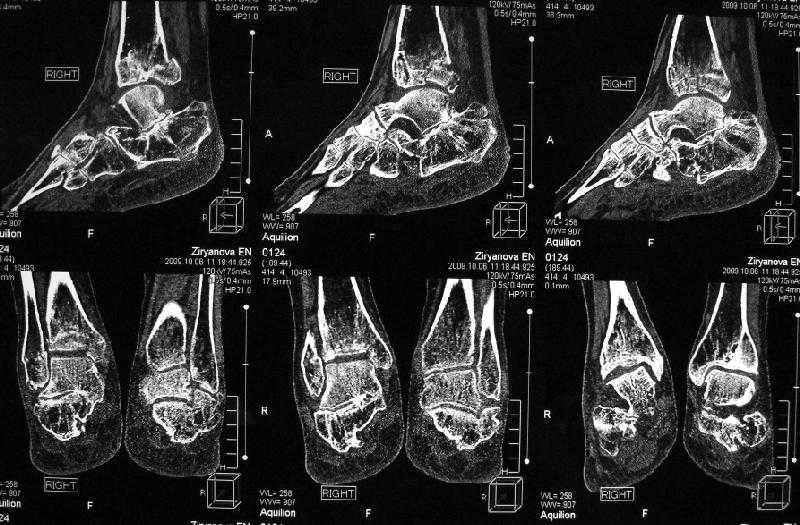

Уважаемые коллеги! Помогите определится с тактикой лечения.Оскольчатый импрессионный перелом заднего края правой большеберцовой (Пилон?) кости 5-ти недельной давности на фоне неправильно сросшихся переломов пяточных костей (травма в 1991г.), ДОА подтаранных суставов 3 ст. До последней травмы больная ходила без особых проблем и работала пекарем (работа на ногах).Суть проблемы в том, что открытая анатомическая репозиция в таком сроке представляется мне крайне травматичной, что может привести к неблагоприятному функциональному исходу.Варианты решения:1) оставить "как есть" с последующим артродезом после развития ДОА2) выполнить остеотомию и попытаться низвести основную часть суставной поверхности3) выполнить попытку анатомической репозиции из задне-латерального??? доступа.

По снимкам довольно сохранный сустав, и такой сустав желательно попытаться восстановить всеми возможными мерами.

Насчет пилона, прошло достаточное время для консолидации и прекрасная возможность для демонстрации, что такие случаи могут быть успешно вылечены остеотомией, несмотря на засторелость.

Из заднего доступа остеотомия тонким остеотомом и коррекции на ЭОПе.

Подобные скиаграммы я рисовал до КТ. На картинке получается красиво, но на деле задний край не имеет единой суставной поверхности и не понятно что и на сколько низводить. Рискуем получить "+ ткань" в суставе, а это ещё хуже.